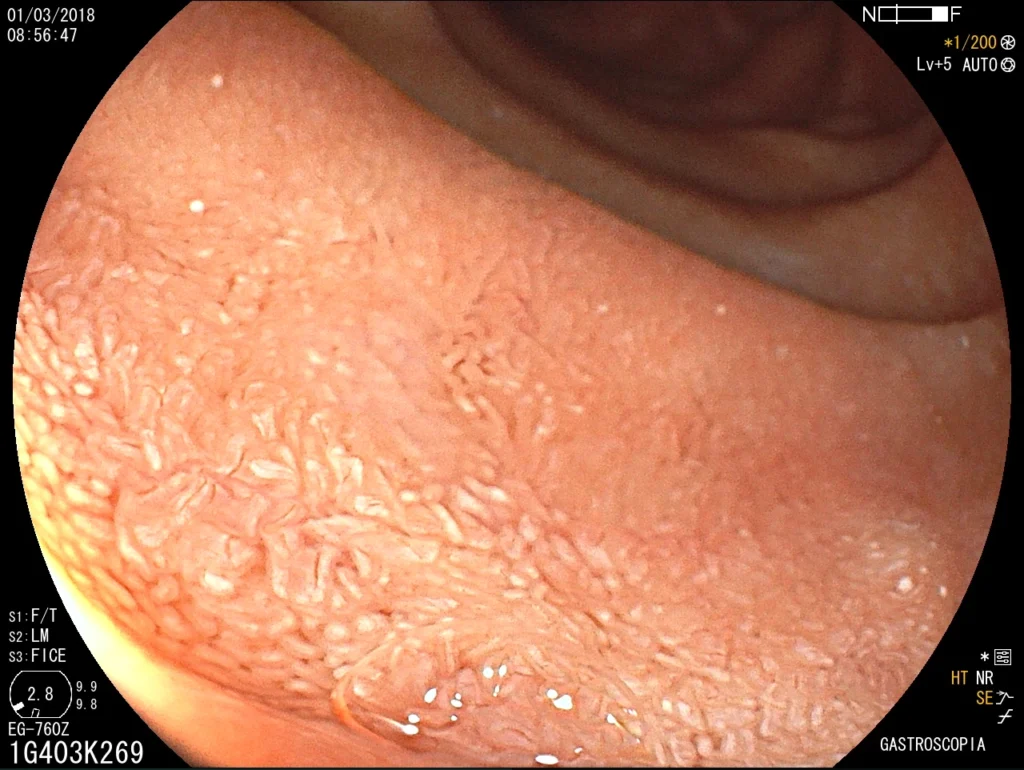

Introducción del gastroscopio bajo visión directa para examinar esófago, estómago y duodeno.

Toma de biopsias de mucosa gástrica o de lesiones encontradas.